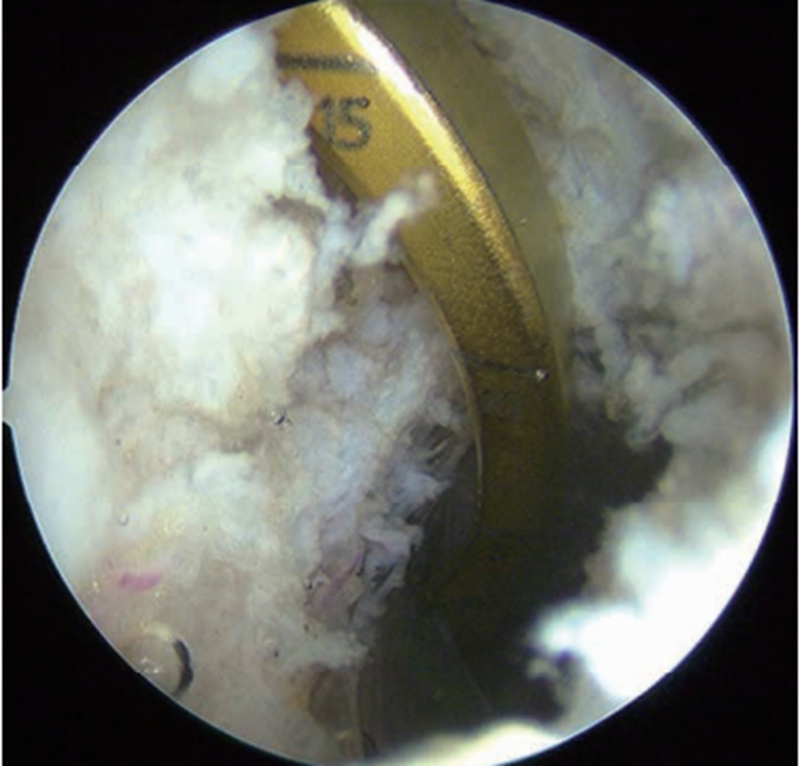

胫骨隧道外口放置在胫骨嵴偏外侧(图10),能更好地减少PCL移植物转折角以及在胫骨隧道内口的接触应力,降低韧带磨损或过度负荷。以后内侧入路为观察通道,从后外侧入路插入关节镜通道鞘管以保护后方血管、神经。直视下打入导针后,用移植物同号直径空心钻制备胫骨隧道。预置牵引线,并将关节镜通道鞘管置入牵引线前方以备协助牵拉移植物经过隧道。牵引线穿过胫骨和股骨隧道,在后方关节镜鞘的辅助牵引下将移植物引至合适位置。先固定股骨侧,固定胫骨侧前应将膝关节置于0°~30°屈伸范围,向前托起胫骨,避免其后坠,用9.1kg(20lb)的力量拉紧移植物并将其固定于胫骨侧(图11)。

图10 PCL胫骨隧道外口

在胫骨嵴外侧定位PCL胫骨隧道外口(左膝)